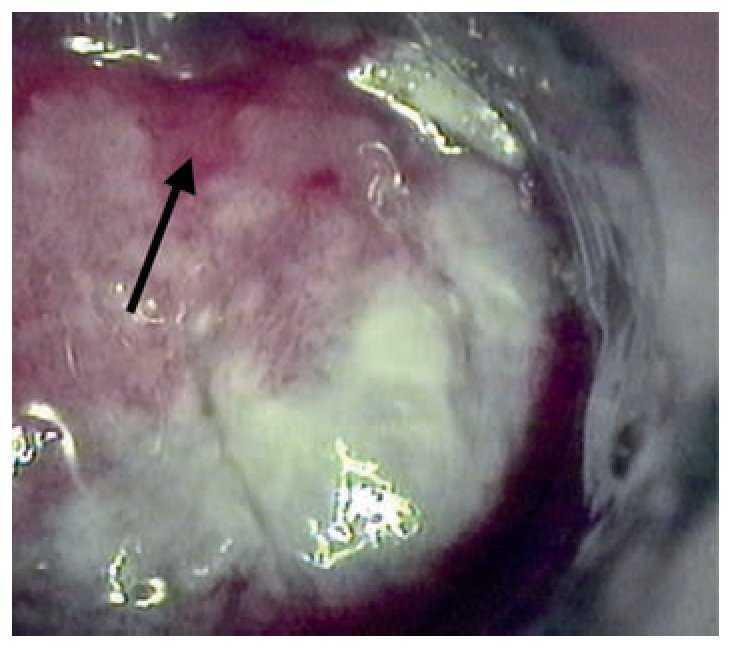

La anoscopia de alta resolución se realizó mediante la siguiente técnica: previa firma del consentimiento informado y con paciente en posición proctológica, se realizó tacto rectal para dilatación del ano, se introdujo anoscopio y se revisó el conducto anal en búsqueda de lesiones macroscópicas. Se aplicó ácido acético a 3% con un hisopo y se retiró el anoscopio. El hisopo se dejó en contacto con las paredes el conducto anal por un minuto y se retiró. Se introdujo nuevamente el anoscopio y se realizó la observación del conducto anal con microscopio de alta resolución. En los casos que se consideró necesario, a criterio del colposcopista, se utilizó la prueba de Schiling para detectar las lesiones sospechosas. Esta prueba consiste en aplicar una solución yodoyodurada de lugol a 1% o 2%, con el objeto de obtener imágenes yodo negativas (que no fijan el lugol), yodo positivas o yodo débiles (que fijan el lugol). El fundamento es que únicamente los tejidos maduros, provistos de glucógeno fijan el yodo, razón por la que el epitelio maligno o atípico es yodo negativo (Figuras 1-3). En las lesiones que resultaron dudosas para VPH o NIA se tomaron 1 o 2 biopsias de la lesión sospechosa. Previo al procedimiento, los pacientes acudieron con preparación intestinal a base de enemas de fosfato. No se administró profilaxis antibiótica y el procedimiento se realizó sin anestesia.

Figura 3. Lesiones del conducto anal que se les aplicó lugol (prueba de Schiling). Las lesiones se tornan de color mostaza